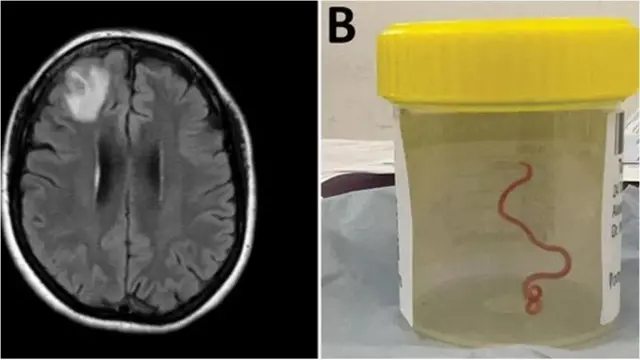

दिमाग़ में मिला ज़िंदा कीड़ा

इमेज स्रोत, Australian National University

दुनिया में पहली बार वैज्ञानिकों ने ऑस्ट्रेलिया की एक महिला के दिमाग़ से 8 सेंटीमीटर (3 इंच) लंबा एक ज़िंदा कीड़ा निकाला. 'लड़ी जैसा दिखने वाला ये कीड़ा', कैनबरा में पिछले साल सर्जरी के दौरान मरीज़ के ज़ख़्मी फ्रंटल लोब से निकाला गया था. लेकिन, इस सर्जरी की पूरी रिपोर्ट इस साल प्रकाशित की गई है.

महिला की सर्जरी करने वाली डॉक्टर हरी प्रिया बंडी ने कहा, "ये तो हमारे वहम-ओ-गुमान में भी नहीं था कि मस्तिष्क के भीतर हमें इतना बड़ा कीड़ा मिल जाएगा."

64 साल की ये महिला कई महीनों से पेट के दर्द, खांसी और रात में पसीना आने जैसी परेशानियों से जूझ रही थी. धीरे-धीरे वो डिप्रेशन और भूलने की बीमारी की शिकार हो गई.

साल 2021 में जनवरी महीने आख़िरी दिनों में उसे अस्पताल में भर्ती कराया गया. स्कैन से उसके दिमाग़ के दाहिनी फ्रंटल लोब के भीतर अजीब तरह की चोट होने का पता चला.

मगर, मरीज़ के मस्तिष्क को ये चोट क्यों लगी, इसकी असल वजह जून 2022 में तब जाकर सामने आई, जब डॉक्टर बंडी ने उनकी बायोप्सी की.

डॉक्टरों ने बताया कि लाल रंग का ये परजीवी, शायद पिछले दो महीनों से उस महिला के दिमाग़ में पल रहा था.

इस मामले की जानकारी दुनिया को देने वाली इमर्जिंग इन्फेक्शस डिज़ीजेस पत्रिका के रिसर्चरों ने कहा कि इस महिला का ये मर्ज़ दुनिया का शायद ऐसा पहला मामला है, जब किसी इंसान के दिमाग़ के भीतर लार्वा की घुसपैठ का पता चला हो.

रिसर्चरों ने चेतावनी दी है कि ये मामला, जानवरों से इंसानों तक पहुंच रही बीमारियों और संक्रमणों के बढ़ते ख़तरे की तरफ़ इशारा करता है.